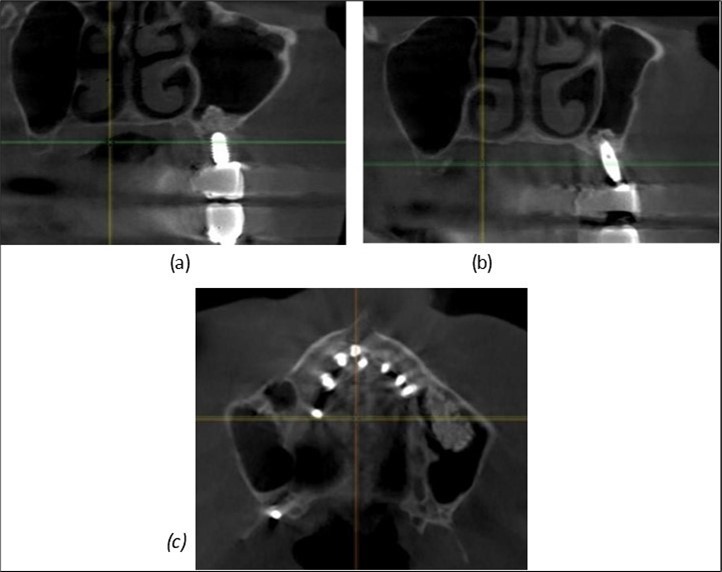

Figure 9.Implants in the pterygoid plateau area: (a) TPG implant fixed in the maxillary-sphenoid junction area, quadrant 1; (b) TPG implant fixed in the maxillary-sphenoid junction area, quadrant 2.

Figure 10.Implants in the palatal sinus cortical area to avoid bone grafting: (a) BCS implant partially fixed in the graft material mass, partially in the palatal cortex; (b) Implant fixed in the palatal cortex at the junction with the nasal cortex, behind the graft material mass.